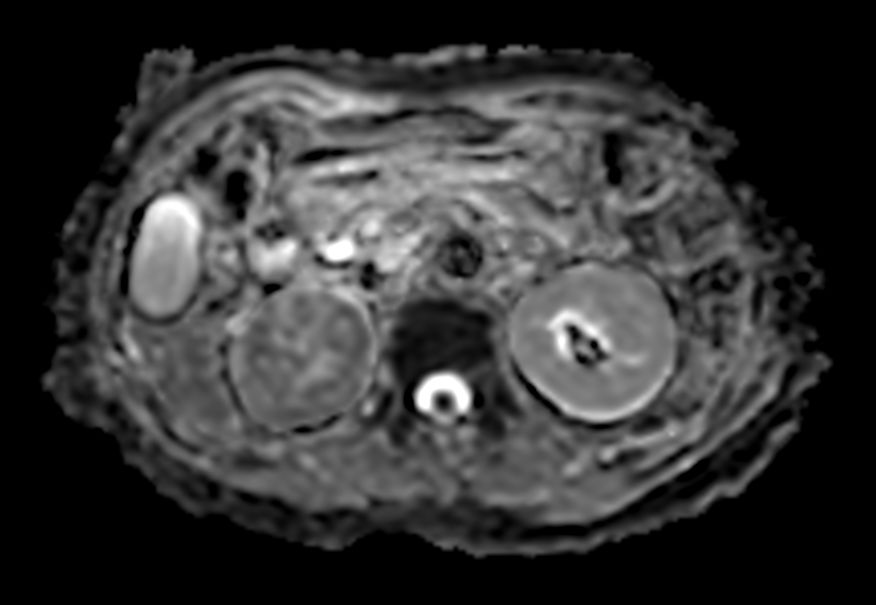

Diffusion b800 - Free Breathing

-